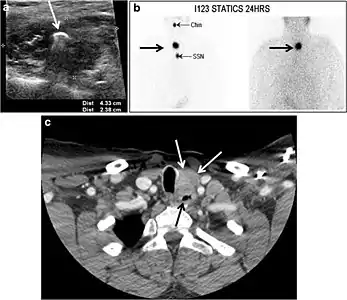

Fig. 17. Ectopic thyroid on the left parotid gland with a palpable left parotid mass in a 69-year-old male patient. a, b Axial and coronal enhanced neck CT scan demonstrates well-defined homogeneous enhancing mass (white arrows) within the left parotid gland with preserved surrounding fat planes. It also shows a normal thyroid in normal position in the lower neck. c Image taken 20 minutes after 5 mCi injected Tc99m-Pertechnetate shows normal thyroid uptake of tracer and physiological uptake in the salivary glands (short black arrow). There is a distinct focus of abnormal tracer accumulation in the left parotid/submandibular region. Patient was given lemon juice with evident normal washout from the salivary glands and relative retention by this abnormal focus (long black arrow).[1]

Fig. 18. Lingular thyroid in a 33-year-old male who presented with oropharyngeal bleeding. an Axial enhanced neck CT scan at the level of mandible demonstrates a 3 × 3 × 3.4 cm round, partly well-delineated, heterogeneously enhancing lesion (white arrow). It is predominantly on the left side of the oropharynx and to some extent at the mid part of the base of the tongue. The thyroid gland was normal (not shown). b Image of the anterior face and neck taken 20 minutes after Tc99m-Pertechnetate injection shows absent thyroid radiotracer uptake in normal thyroid anatomical location (black short arrows). There is an area of increased uptake (long black arrows) corresponding to the posterior tongue mass identified on CT scan.[1]